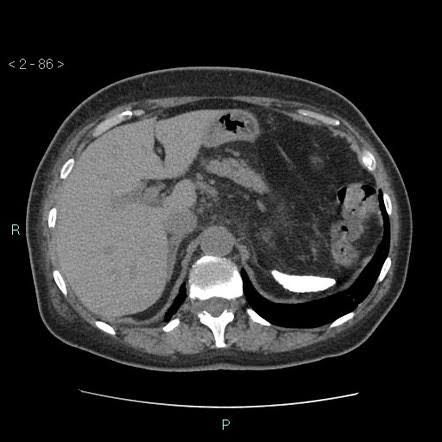

Auto-splenectomy is a well-known complication of sickle cell disease; which is caused by micro vascular occlusion by deformed red blood cells which leads to ischaemia and infarction. Repeated infarctions lead to necrosis and gradual resorption of spleen.